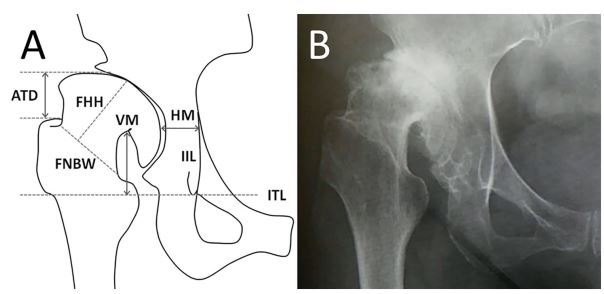

图1:VM为泪滴间线与股骨头颈交界处的垂直距离。HM为股骨头内侧缘与髂坐线之间的水平距离。ATD为大转子尖端与股骨头上缘的垂直距离。